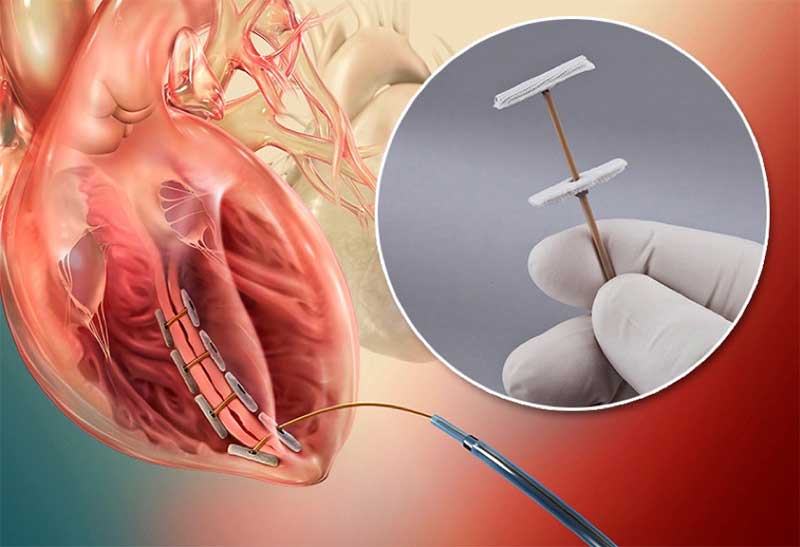

Fortunately, recent advances in medical engineering have produced a less invasive and less complicated alternative to SVR, and this is one area where PEEK polymer comes in. The SVR alternative is a procedure developed by BioVentrix, a medical device manufacturer, and is known as Less Invasive Ventricular Enhancement (LIVE). LIVE has already been performed on more than 50 patients successfully, though it has only been available for a short time.

During a LIVE procedure, a pair of anchors, connected by a PEEK tether, are positioned adjacent to left ventricle scarring. The internal anchor is placed percutaneously and over the scar tissue. The external anchor is positioned on the left ventricle epicardium. The PEEK tether connects the two anchors, provides traction and ensures the anchors remain in alignment. Together, the anchors and tether help position the left ventricle wall, and restore proper circulation.

The LIVE procedure demands materials that can withstand the constant movement exerted by the heart’s beating. PEEK’s strength has been proven in some of the most demanding applications imaginable, making it an ideal option for LIVE.

PEEK and PAEK can be fabricated in extremely small sizes, so they can be used to produce very small medical components. PAEK’s processing versatility allows components to be manufactured down to extremely small dimensions, which makes it a strong choice for less invasive procedures, and PEEK’s role in the LIVE procedure means surgeons have an alternative to cardiopulmonary bypass and risky heart incisions. PEEK can be produced in thicknesses of only .040 in. and be fabricated to rectangular shapes just .040 in. wide x .065 in. deep x 12 in. long.